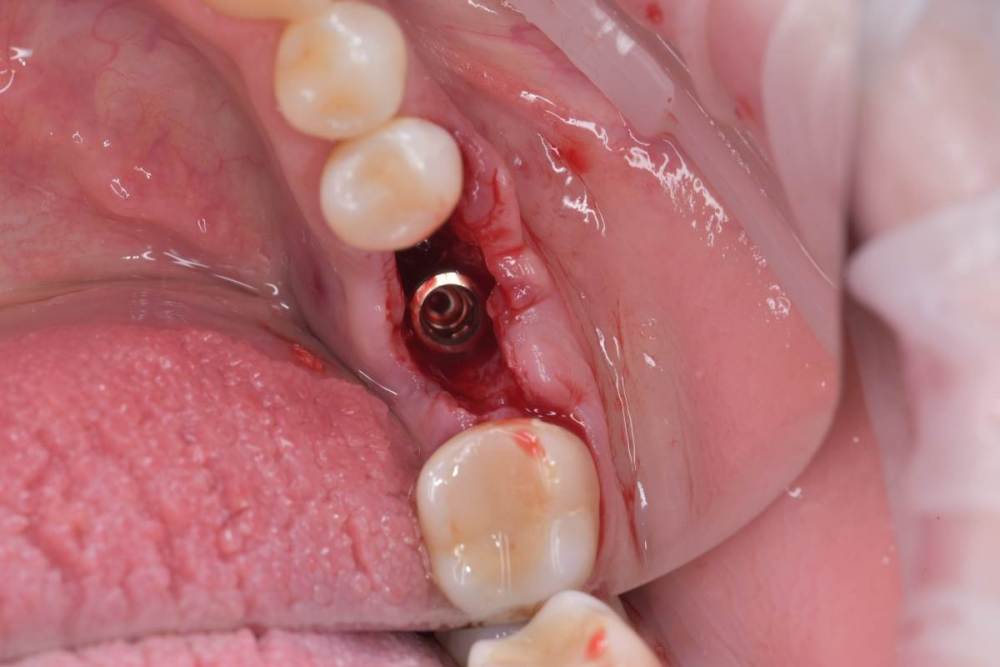

TIGER Опубликовано 22 сентября, 2022 Поделиться Опубликовано 22 сентября, 2022 Всем привет!Давно ничего не закидывал,небольшой клинический случай,банальщина,замещение одиночного моляра,система Straumann понравилась,как всегда только оригинальные компоненты? 8 1 Ссылка на комментарий

TIGER Опубликовано 1 октября, 2022 Автор Поделиться Опубликовано 1 октября, 2022 (изменено) @annda да,вы про лунку?похоже,согласен,шейка широкая там 4.8 диаметр,но если присмотреться на внутренности видно,что это не SynOcta)А конус Изменено 1 октября, 2022 пользователем TIGER 1 Ссылка на комментарий